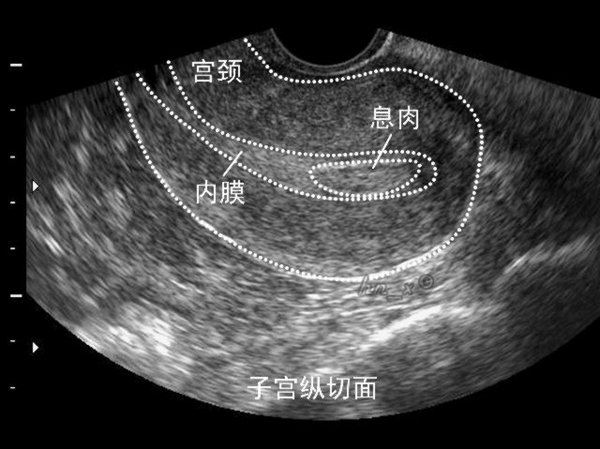

1、子宫内膜息肉是一种常见的妇科疾病, 是子宫局部内膜过度生长的结果,可谓是宫腔里的不速之客。无症状女性常在体检(或因其他疾病如不孕,月经不规律做检查)时意外发现子宫内膜息肉。年龄增长与激素补充治疗是其高发主要原因。子宫内膜息肉有复发的倾向(2.5%-3.7%)。子宫内膜息肉不仅仅只有手术治疗,如果息肉较小,直径<1层面,且无症状,可以观察随诊。一年内自然消失吕伟率为27%。你刚做过手术,我不建议短期内再次手术,可以观察一段时间。

对你来说,子宫内膜息肉也可以影响月经,导致月经间期出血,月经过多,或不规则出血,甚至不孕。你已做息肉手术,建议先观察一段时间。另外,还应排除精神因素造成的月经不调。你正在做生育准备,往往会过度关注月经,精神压力过大,也可引起月经的一些变化。

子宫是孕育胎儿的暖房。在这一亩二分地上,任何不速之客都是不受欢迎的。对于患有息肉的不孕妇女,手术切除息肉有助于增加受孕的几率。据研究报道,进行试管婴儿的不孕妇女,子宫内膜息肉患病率为32%。也就是说,子宫内膜息肉与不孕有着密切联系。你已经做过两次手术,再次手术需要慎重。观察一段时间也是必要的,因为小的息肉可以自然消失。